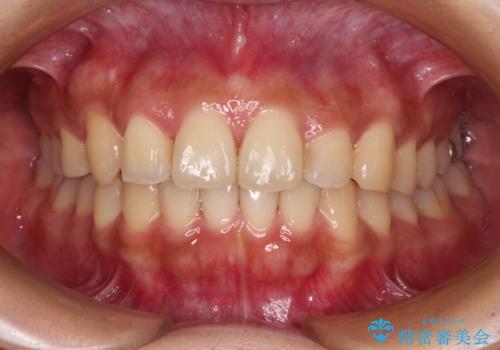

【モニター】歯列が狭くデコボコが気になる 急速拡大装置を用いたインビザライン矯正

上顎骨の幅が下顎骨よりも小さいので、拡大装置により骨幅を広げて上下関係を改善し、その後インビザラインにて歯並びを整えることとしました。

上下の骨幅を改善したことで、スムーズに歯列矯正を行うことができました。

土台のまま放置されていた歯は土台の状態で咬み合っていましたが、急速拡大を行った際に咬み合わせが著しく挙上されたため、その際に土台を大きくすることで咬み合う歯との距離を確保しました。